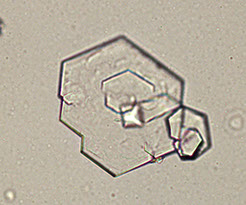

Cystine

Cysteine - assoc c a cysteine calculus and some metabolic disorders

- transparent, refractile hexagonal plates that are variably-sized